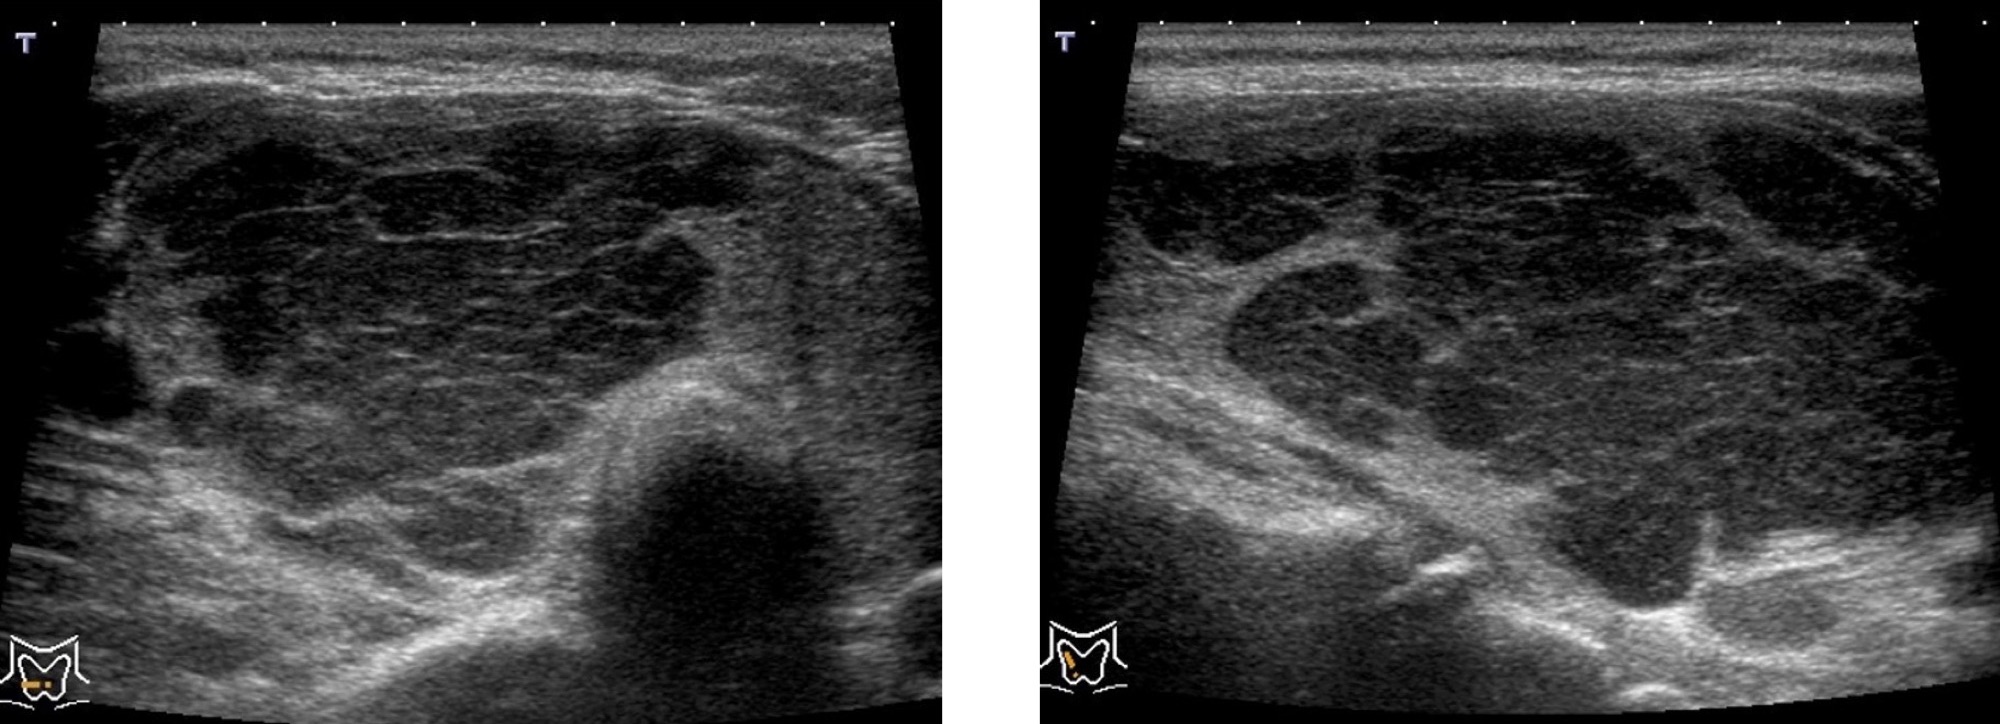

リンパ腫

形がいびつ(形状不整)で、内部が黒く(内部エコーレベル低)、腫瘍の後ろの方が白っぽく見えます(後方エコー増強)。